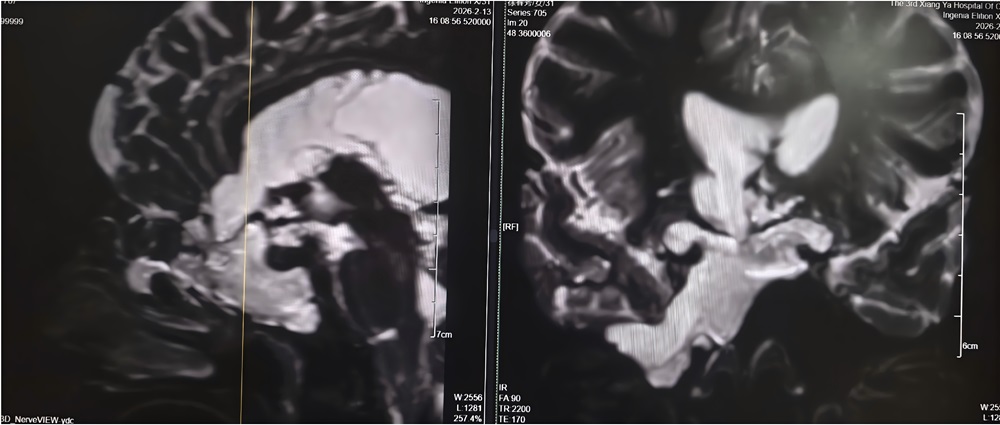

湘雅三医院功能神经外科副主任医师杨靓团队接诊后,第一时间为其完善影像及实验室检查。经系统评估与综合分析,专家团队明确诊断刘女士所患疾病为——与脑室相通的高流量脑脊液漏,且其颅内感染情况较为严重。

团队指出,此类高流量脑脊液漏病情复杂,治疗难度极高:若直接进行修补手术,术后极易因颅内压力过高导致修补失败;同时,若在感染未充分控制前贸然封堵漏口,可能因失去引流通道导致颅内压骤升,进而造成病情急剧恶化,甚至危及患者生命。为确保治疗安全有效,经多学科讨论后,专家团队为刘女士量身制定了“先引流控制感染,后精准修补漏口”的阶梯式治疗方案,分阶段推进救治工作,最大限度降低治疗风险。